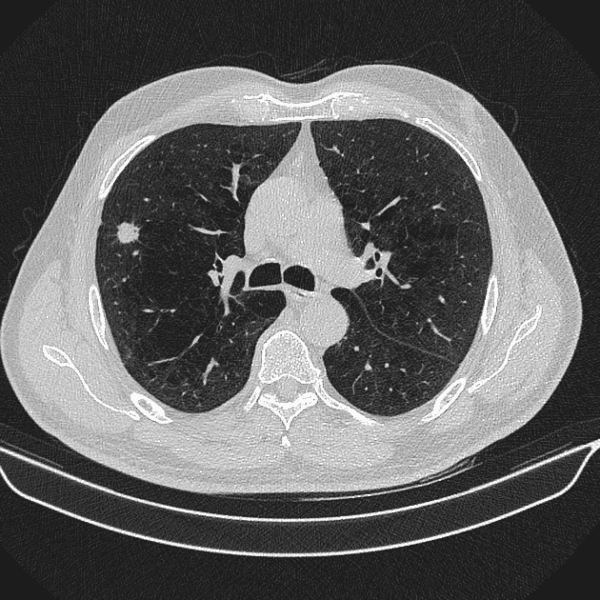

U phổi

» Thông tin: Nam giới – 70 tuổi.

» Lâm sàng: Ho / Tiền sử hút thuốc lá.

# Ung thư biểu mô tuyến (Adenocarcinoma).